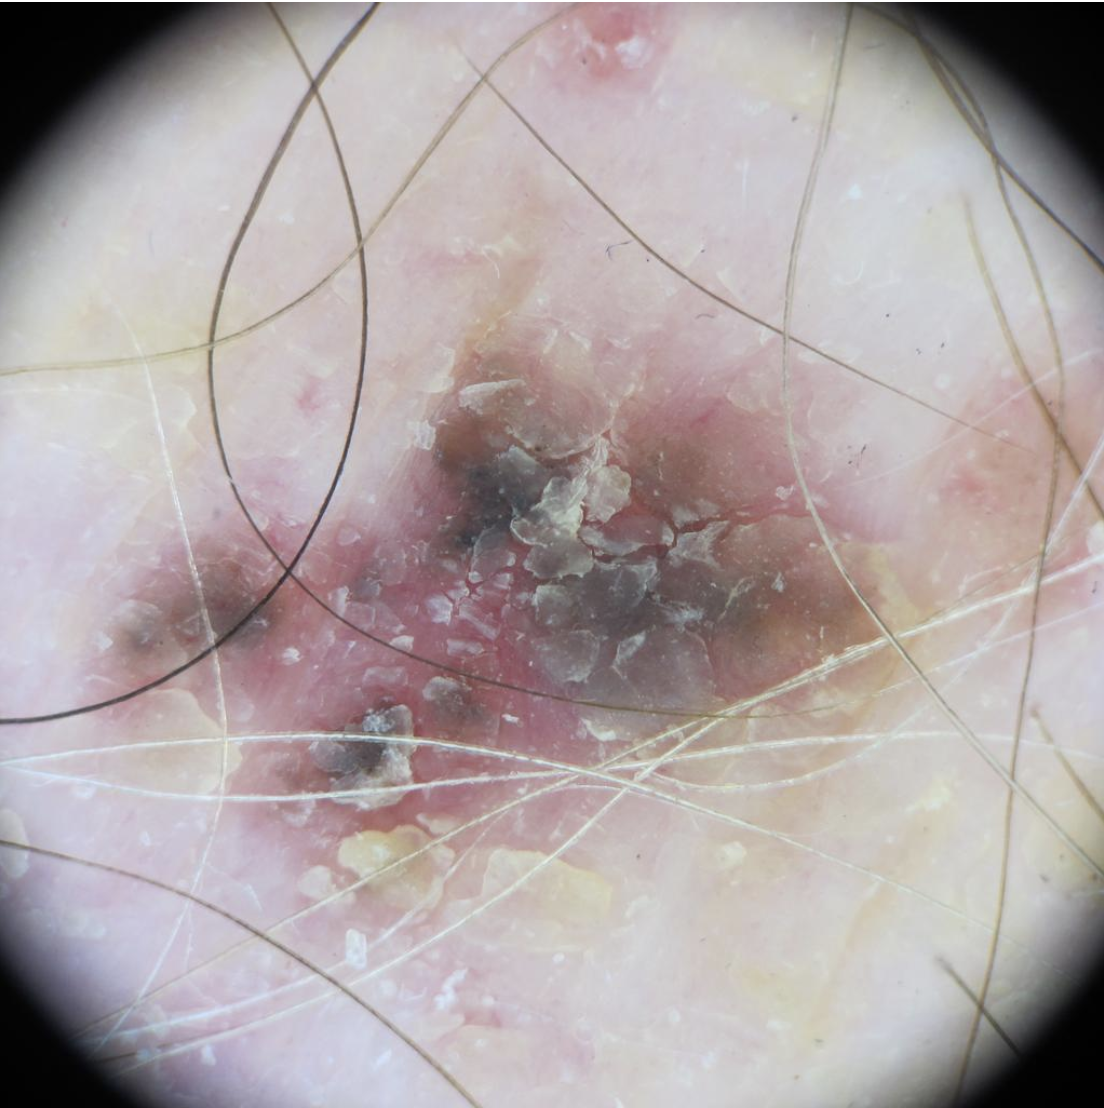

Nodular melanoma on the leg of a Native American woman.

Photo: International Skin Imaging Collaboration

Amelanotic melanomas may be pinkish-looking, reddish, purple, normal skin color or essentially clear and colorless.